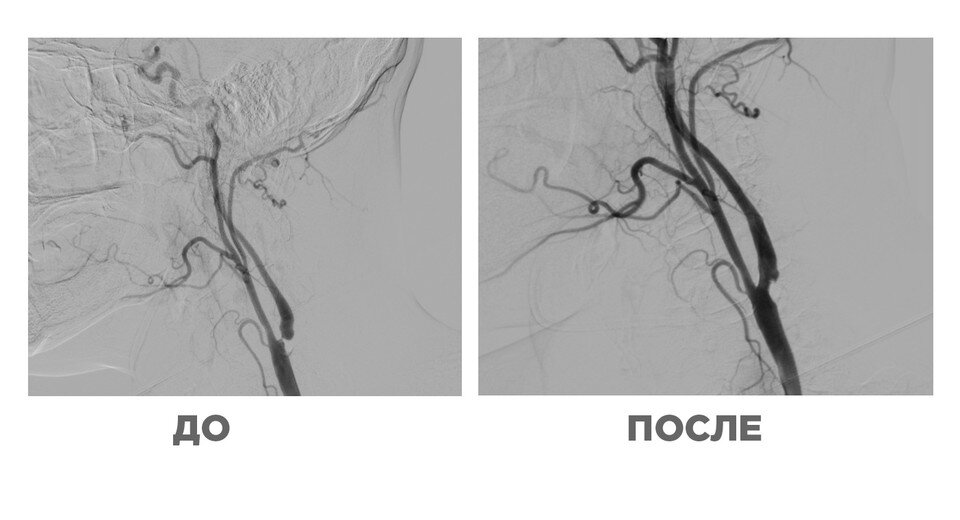

Медики провели ультразвуковое исследование сонной артерии и нашли бляшку, которая перекрыла 90% кровотока. После этого пациента отправили на мультиспиральную компьютерную томографию сонных артерий и артерий головного мозга, выяснилось, что у мужчины также есть закупорка артерии на 95%. Специалисты установили в артерию специальную ловушку, операция прошла успешно.

Фото: Пресс-служба Минздрава Московской области